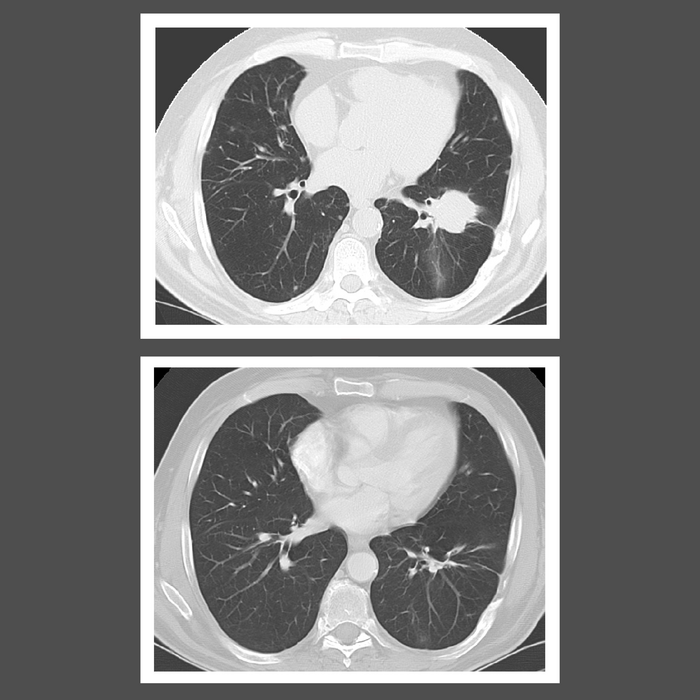

Lymphomatoid granulomatosis causes an overproduction of white blood cells known as B lymphocytes. Patients typically have lesions in the lungs, central nervous system, skin, liver, and kidneys. Symptoms can include cough, shortness of breath, fever, weight loss, and fatigue. Chemotherapy is currently the standard treatment for people with high-grade disease, but there is no standard treatment for low-grade disease.